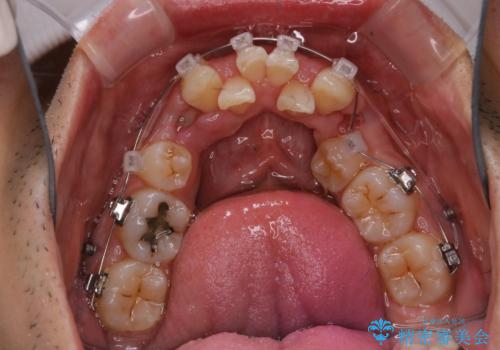

- ワイヤー装置で矯正中の方です。歯磨きがしずらく、専門的な機械でクリーニングしてほしいとの事でした。PMTC60分コースを行いました。

ワイヤー矯正中はブラッシングが難しくなるため、磨き残しが多くなることがあります。適切な道具を使って、適切なブラッシング方法を習得することで、磨き残しを減らすことができます。

また、矯正で歯の移動があると今までなかったところに隙間が出てきたり、ガタつきが解消されてきたりすることで、お口の中の環境が変わります。

矯正治療中も清潔な口腔内を保つことは、とても大切です。そのため、定期的に専門的な機械・材料を使用したProfessinnalcleaning(pmtc)を行うことがおススメです。